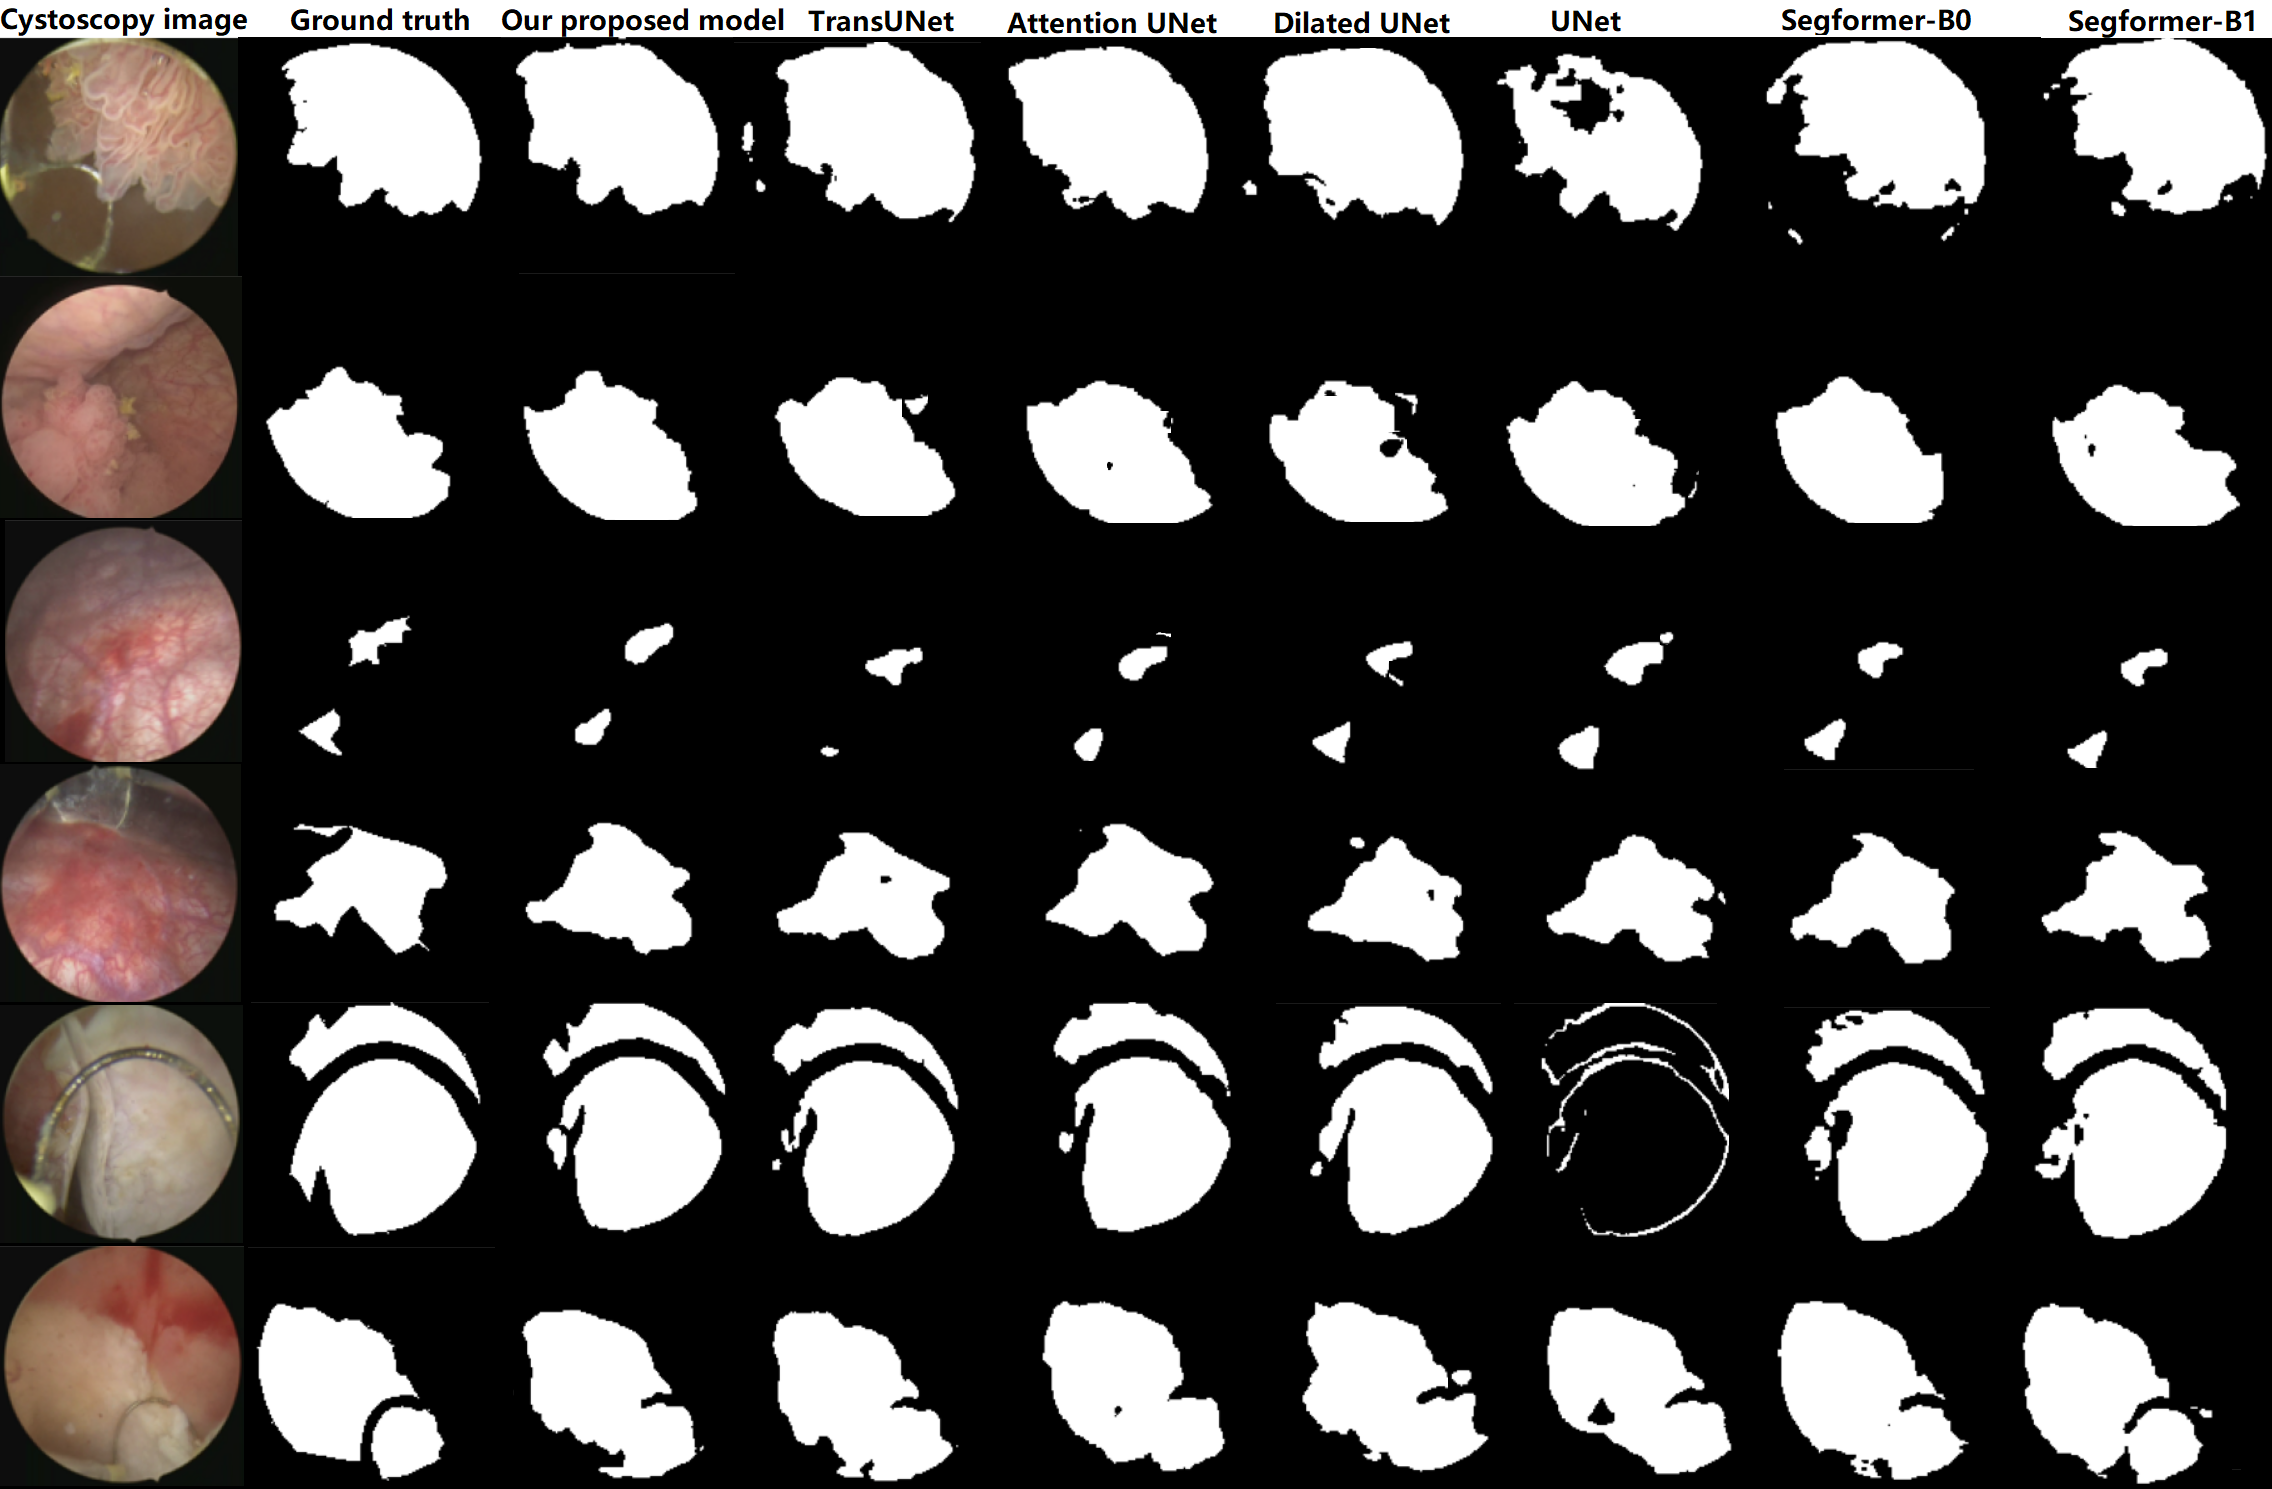

Refer to caption

Fig. 5: Visual comparison with UNet, Dilated UNet, Attention UNet, TransUNet and Segformer-(B0,B1) on cystoscopy images.

After training on our Cystoscopy dataset, our model achieved an accuracy of 96.9%percent96.996.9\%, IoU of 85.7%percent85.785.7\%, and a DC of 92.0%percent92.092.0\%, all while maintaining a compact size with only 367234367234367234 parameters. It outperforms UNet, Dilated UNet, and Attention UNet in terms of DC, IoU, and accuracy. Our model achieves competitive performance, even compared to TransUNet, which has significantly more parameters. Additionally, when considering lightweight architectures like Segformer B0 and B1, our model achieves better results despite having fewer parameters, making it suitable for resource-constrained scenarios. The comparative results are summarized in Table 4. In summary, our strategic architectural decisions, allowed us to achieve a good performance while maintaining a highly efficient and lightweight model. This demonstrates the effectiveness of our approach in achieving a balance between model size and segmentation accuracy, even when compared to the lightest versions of Segformer, B0 and B1.

Fig. 5 provides a comprehensive visual comparison of segmentation results. Upon visual examination, it becomes readily apparent that our model demonstrates a good precision in predicting boundaries. The visual analysis clearly reveals that our model’s segmentation contours exhibit great accuracy and align closely with the true boundaries.